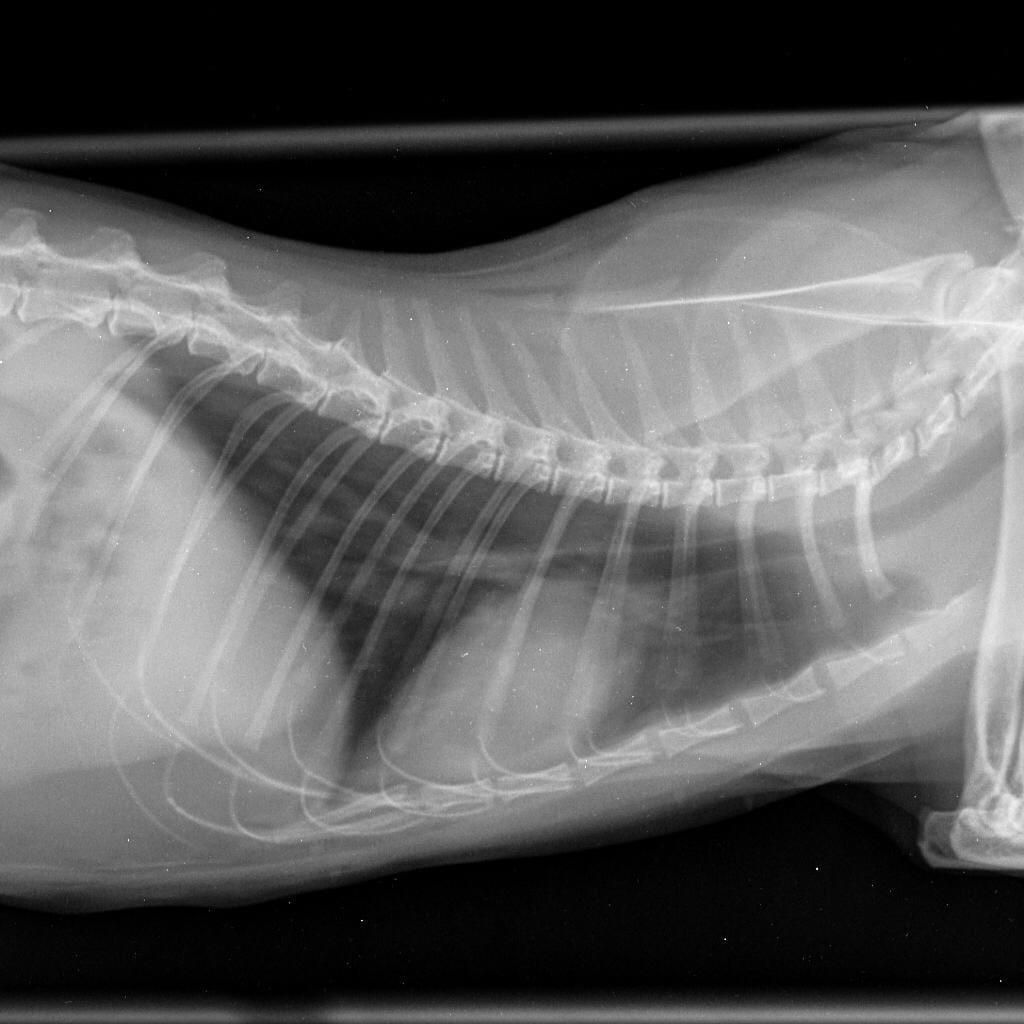

Истончение костей у кошек: причины и решения

Раздел: Мудрость в объективе